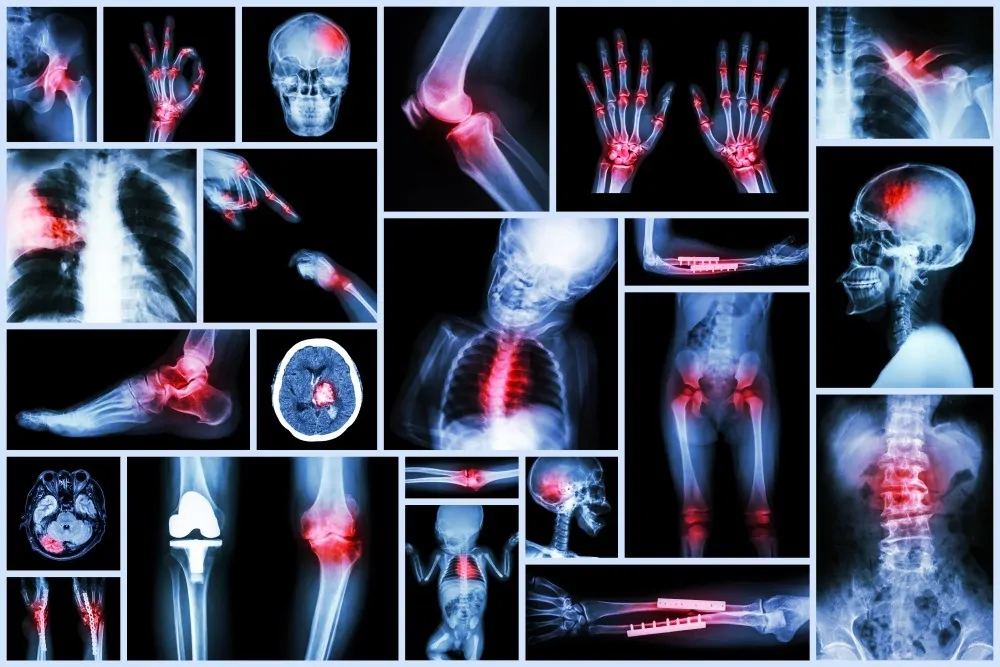

Trauma & Emergency Orthopedic Care at Pure Ortho Hospitals

In cases of accidents, fractures, or severe injuries, timely medical intervention can make all the difference. At Pure Ortho Hospitals, our Trauma & Emergency Orthopedic Centre is fully equipped to provide comprehensive, round-the-clock care for patients with critical injuries and complex fractures. From rapid life-saving stabilization to advanced orthopedic surgeries, our expert team ensures precise and efficient treatment tailored to each patient’s needs. Post-surgery, personalized rehabilitation programs help patients regain mobility and strength quickly, promoting a smoother recovery. By combining cutting-edge technology, skilled orthopedic specialists, and compassionate care, we deliver complete, seamless treatment under one roof where every patient’s safety and well-being is our top priority.

Orthopedic trauma refers to serious injuries to the bones, joints, ligaments, muscles, or soft tissues caused by accidents, falls, sports injuries, or high-impact collisions. Immediate and accurate treatment is vital to:

Comprehensive Trauma Care Services

Our Trauma Centre handles a wide range of emergency orthopedic cases with a focus on precision and safety.